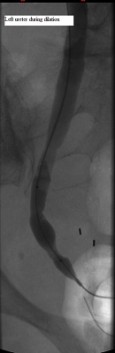

Distal left ureter during dilation

Published July 12, 2014 at 115 × 353 in Bilateral insertion of nephroureteral stents after balloon dilation of malignant obstruction of the distal ureters. Ken U. Ekechukwu, MD, MPH, FACP..